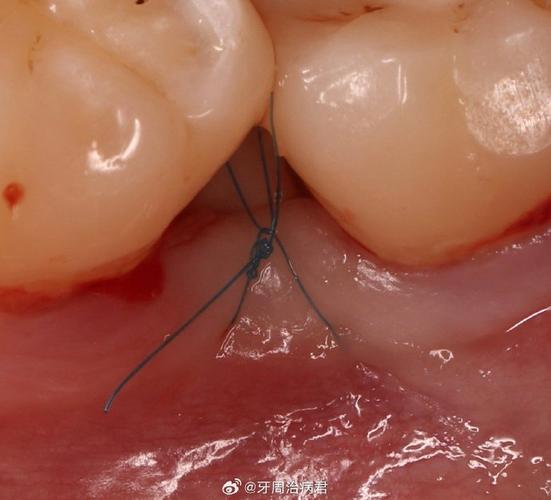

(图片来源网络,侵删)

悬吊缝合 (Suspension Suture)

- 适用场景: 主要用于将牙龈瓣(如翻瓣术后的龈瓣)悬吊固定在邻近的牙面或骨面上,以提供初始稳定性、减少死腔、防止瓣下垂,常与间断或连续缝合配合使用。

- 操作步骤:

- 定位: 在需要固定的龈瓣边缘(通常是龈乳头或龈缘处)选择进针点。

- 进针与穿行: 在龈瓣边缘距切缘约1-2mm处垂直刺入针,穿过龈瓣全层。

- 穿过牙间隙: 将针穿过牙间隙,到达邻近的牙面。

- 环绕牙面: 在牙面(通常是釉质或牙骨质)上,环绕牙颈部一周或半周。

- 出针与打结: 将针穿回龈瓣的进针点附近或稍远处,穿出龈瓣,拉紧缝线使龈瓣紧密贴合在牙面或骨面上,打好结。

- 优点: 提供龈瓣的初始稳定性和固位力;有效减少死腔;防止龈瓣移位。

- 缺点: 需要在邻近牙面操作;可能增加患者术后异物感;需注意避免缝线滑脱或切割牙面。